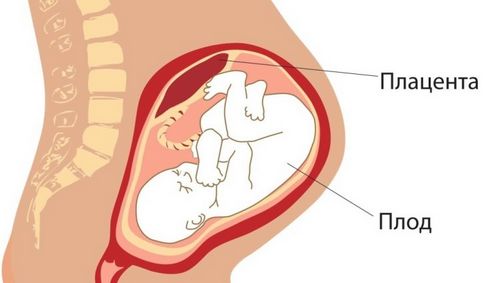

УЗД на цьому терміні, як і на будь-якому іншому, покликане оцінити стан плода і систем його життєзабезпечення. Лікар уважно обстежує дітородні органи вагітної жінки і потім переходить до діагностики стану малюка. На 19 тижні УЗД плоду включає в себе оцінку та порівняння з нормою:

З собою потрібно мати пелюшку - застелити кушетку, і одноразові серветки - видалити залишки гелю. Процедура проводиться в положенні лежачи. УЗД на терміні 19 тижнів проводиться строго трансабдоминально. На цьому етапі вагітності на УЗД оглядають анатомічна будова і стан органів матері і її малюка, а також досліджують кровотік в системі «матка-плацента-плід» за допомогою допплерометрії судин.Що оцінюється при проведенні УЗД?

Далі обстежується з усією увагою стан системи, що забезпечує життя і здоров'я малюка (плацента, пуповина, матка), а також кількість навколоплідних вод. Виключається мало-, багатоводдя.

Оцінюється плацента - її зрілість (нульова на цьому терміні), її стан (відсутність кальциноза і інфарктів), її передлежання (оптимально - на задній стінці матки, варіант норми - передня і бічна стінки матки). Низьке розташування плаценти (менше 7 см. До внутрішнього зіву матки) або перекриття плацентою зіву - це стани, які вважаються патологічними. Вимагає спостереження, а в деяких випадках, оперативного розродження шляхом кесаревого розтину.